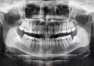

Licówki porcelanowe to jeden z najpopularniejszych zabiegów w stomatologii estetycznej, który pozwala na poprawę wyglądu zębów. Dzięki nim można uzyskać idealny kształt, kolor oraz gładkość, co wpływa na pewność siebie pacjentów. Warto rozważyć ten zabieg ze względu na korzyści estetyczne oraz profesjonalną opiekę wykwalifikowanego personelu w gabinetach takich jak Dental Med Grzegorz Wojcierowski we Wodzisławiu Śląskim i innych miejscach. Przeczytaj dalej, aby dowiedzieć się więcej o zaletach licówek porcelanowych oraz dodatkowych usługach oferowanych przez specjalistów w tej dziedzinie.

Licówki porcelanowe mają pozytywny wpływ na zdrowie zębów, co czyni je korzystnym rozwiązaniem nie tylko z estetycznego punktu widzenia. Dzięki nim można zminimalizować ryzyko uszkodzeń oraz poprawić funkcjonalność uzębienia. Porcelanowe pokrycia chronią naturalne szkliwo przed erozją i pęknięciami, co zmniejsza prawdopodobieństwo wystąpienia problemów takich jak próchnica czy złamania. Ponadto, licówki wspierają zdrowie jamy ustnej poprzez poprawę funkcji żucia i eliminację dyskomfortu podczas spożywania pokarmów.

Warto dodać, że odpowiednia pielęgnacja tych elementów oraz regularne wizyty kontrolne u stomatologa pozwalają utrzymać ich trwałość i uniknąć ewentualnych komplikacji. W ten sposób pacjenci mogą cieszyć się zarówno pięknym uśmiechem, jak i zdrowymi zębami przez długi czas. Licówki porcelanowe to więc inwestycja w estetykę oraz zdrowie jamy ustnej. Dlatego warto również zwrócić uwagę na profilaktykę dentystyczną, aby zapewnić sobie długotrwałe efekty i zdrowe uzębienie.

Licówki porcelanowe to doskonałe rozwiązanie dla osób pragnących poprawić swój uśmiech. Dzięki nim można uzyskać nie tylko estetyczny efekt, ale także poprawić zdrowie zębów. Warto rozważyć ten zabieg oraz skonsultować się z Dental Med Grzegorz Wojcierowski, gdzie wykwalifikowany personel zapewni fachową opiekę na każdym etapie leczenia. Korony protetyczne, mosty porcelanowe, protezy i licówki porcelanowe to tylko niektóre z dostępnych usług w zakresie stomatologii estetycznej. Decydując się na licówki porcelanowe, można cieszyć się pięknym uśmiechem przez długie lata oraz zadbać o zdrowie swoich zębów.